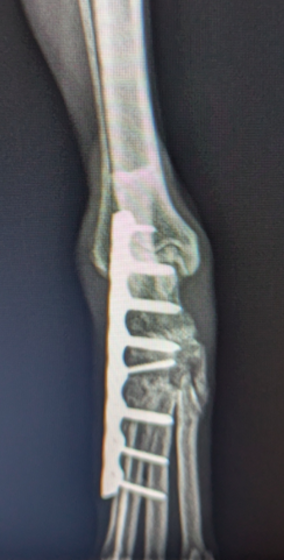

HPの外科の「その他の整形外科疾患」のページに、犬の足根関節の部分関節固定術を追加致しました。(コチラ)足根関節は脛骨、腓骨、踵骨、距骨、足根骨、中足骨と複数の骨で形成され、その関節構造は複雑であり複数の靭帯と腱で安定化されています。足根関節の脱臼や亜脱臼は、主に落下や激しい運動中の外傷によって生じます。症状として、患部は熱感を持って腫れ、動物は痛みにより後肢を挙上したり、負重を避けるように行動します患部g腫れ、動物は痛みにより歩行時や排泄時に体重がかからないように庇。治療法は、軽症の場合は副子や装具による保存療法を行いますが、重症の場合は靭帯修復や関節を固定する関節固定術を行う必要があります。歩行異常や足を庇うような仕草が認められる場合はお早めにご相談下さい。

獣医師 臼井